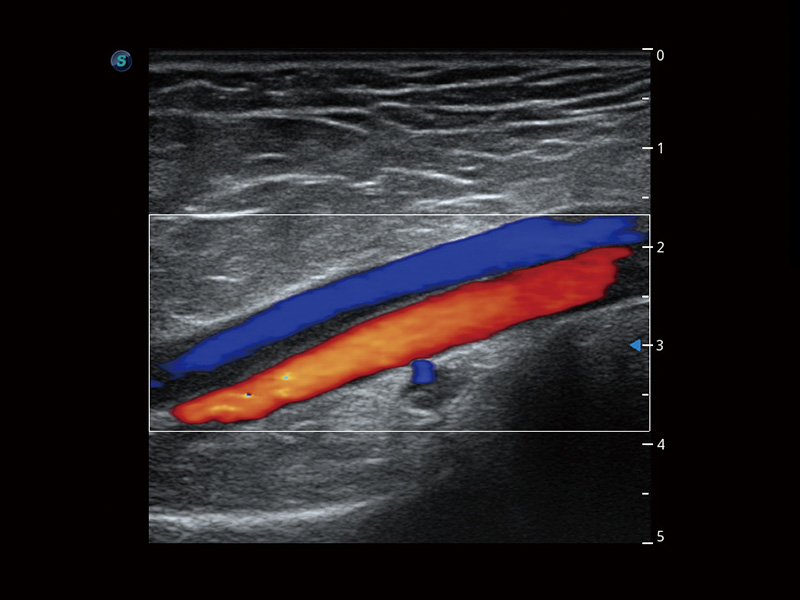

Consente la visualizzazione delle strutture microvascolarizzate

Micro F offre un metodo innovativo per ampliare la portata di flusso visibile nell'ecografia, in particolare per visualizzare l'emodinamica dei piccoli vasi a flusso lento. Grazie all'adozione di un filtro adattivo avanzato e all'accumulo di segnali temporali e spaziali, Micro F è in grado di distinguere in modo efficace il flusso minuto dal movimento di tessuto sovrapposto e di rappresentare l'emodinamica con sensibilità e risoluzione spaziale più elevate.

• Arteria pericallosa fetale con Micro F

• Flusso ematico renale con Micro F

• Nodulo tiroideo con Micro F

• Linfonodo cervicale con Micro F